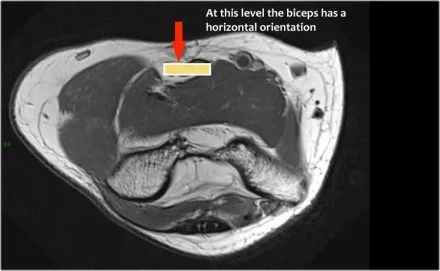

中位神经:正中神经落后于Lacertus纤维,即肱二头肌的腱膜并穿透旋前肌。